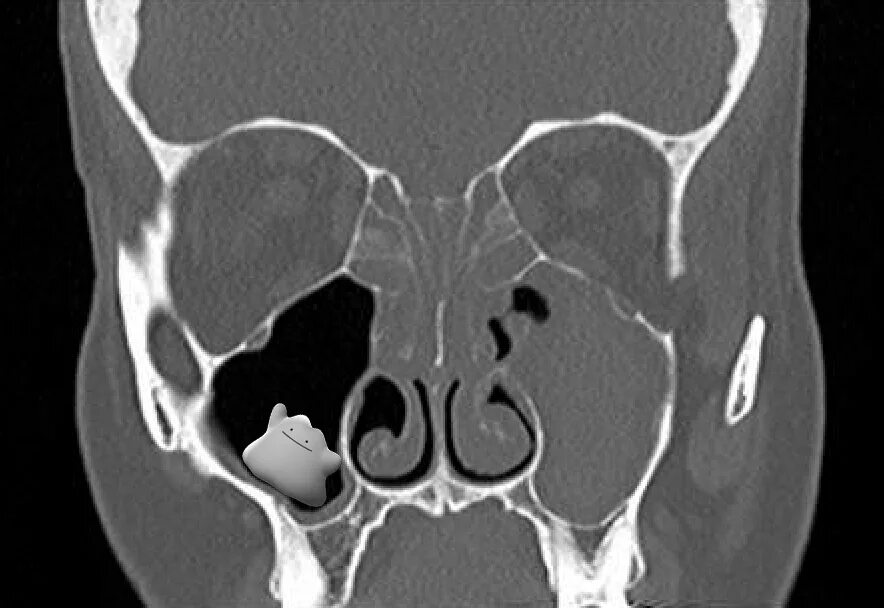

Синусит на кт